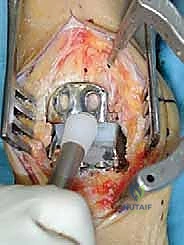

تُجرى العملية عادة تحت التخدير النصفي أو العام، وتستغرق حوالي الساعتين إلى ثلاث ساعات. الدقة هنا تقاس بالمليمترات وأجزاء الدرجة الزاوية.

1. الشق الجراحي والوصول للمفصل

يقوم الجراح بإجراء شق أمامي طولي (Anterior Approach) في منتصف الكاحل. يتم إبعاد الأوتار والأوعية الدموية والأعصاب بعناية فائقة (هنا تتجلى أهمية مهارات الجراحة الدقيقة التي يمتلكها الدكتور هطيف) للوصول إلى محفظة المفصل.

2. إزالة الزوائد العظمية وتحرير المفصل

يتم إزالة النتوءات العظمية (Osteophytes) التي تسبب الألم وتحد من الحركة، وتحرير الأنسجة المتليفة لاستعادة المرونة الأولية للمفصل.